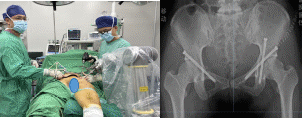

▲手术中以及术后效果图

术中,手术团队依照术前计划,为梁先生实施了“左侧髋臼横形骨折有限切开复位机器人导航下顺行前柱螺钉联合顺行后柱螺钉内固定+右耻骨骨折闭合复位顺行螺钉内固定术”。手术过程顺利,术后,梁先生的病情恢复良好、疼痛感有了明显的缓解,在创伤骨科医护团队的精心治疗和照料下,很快便达到出院标准。